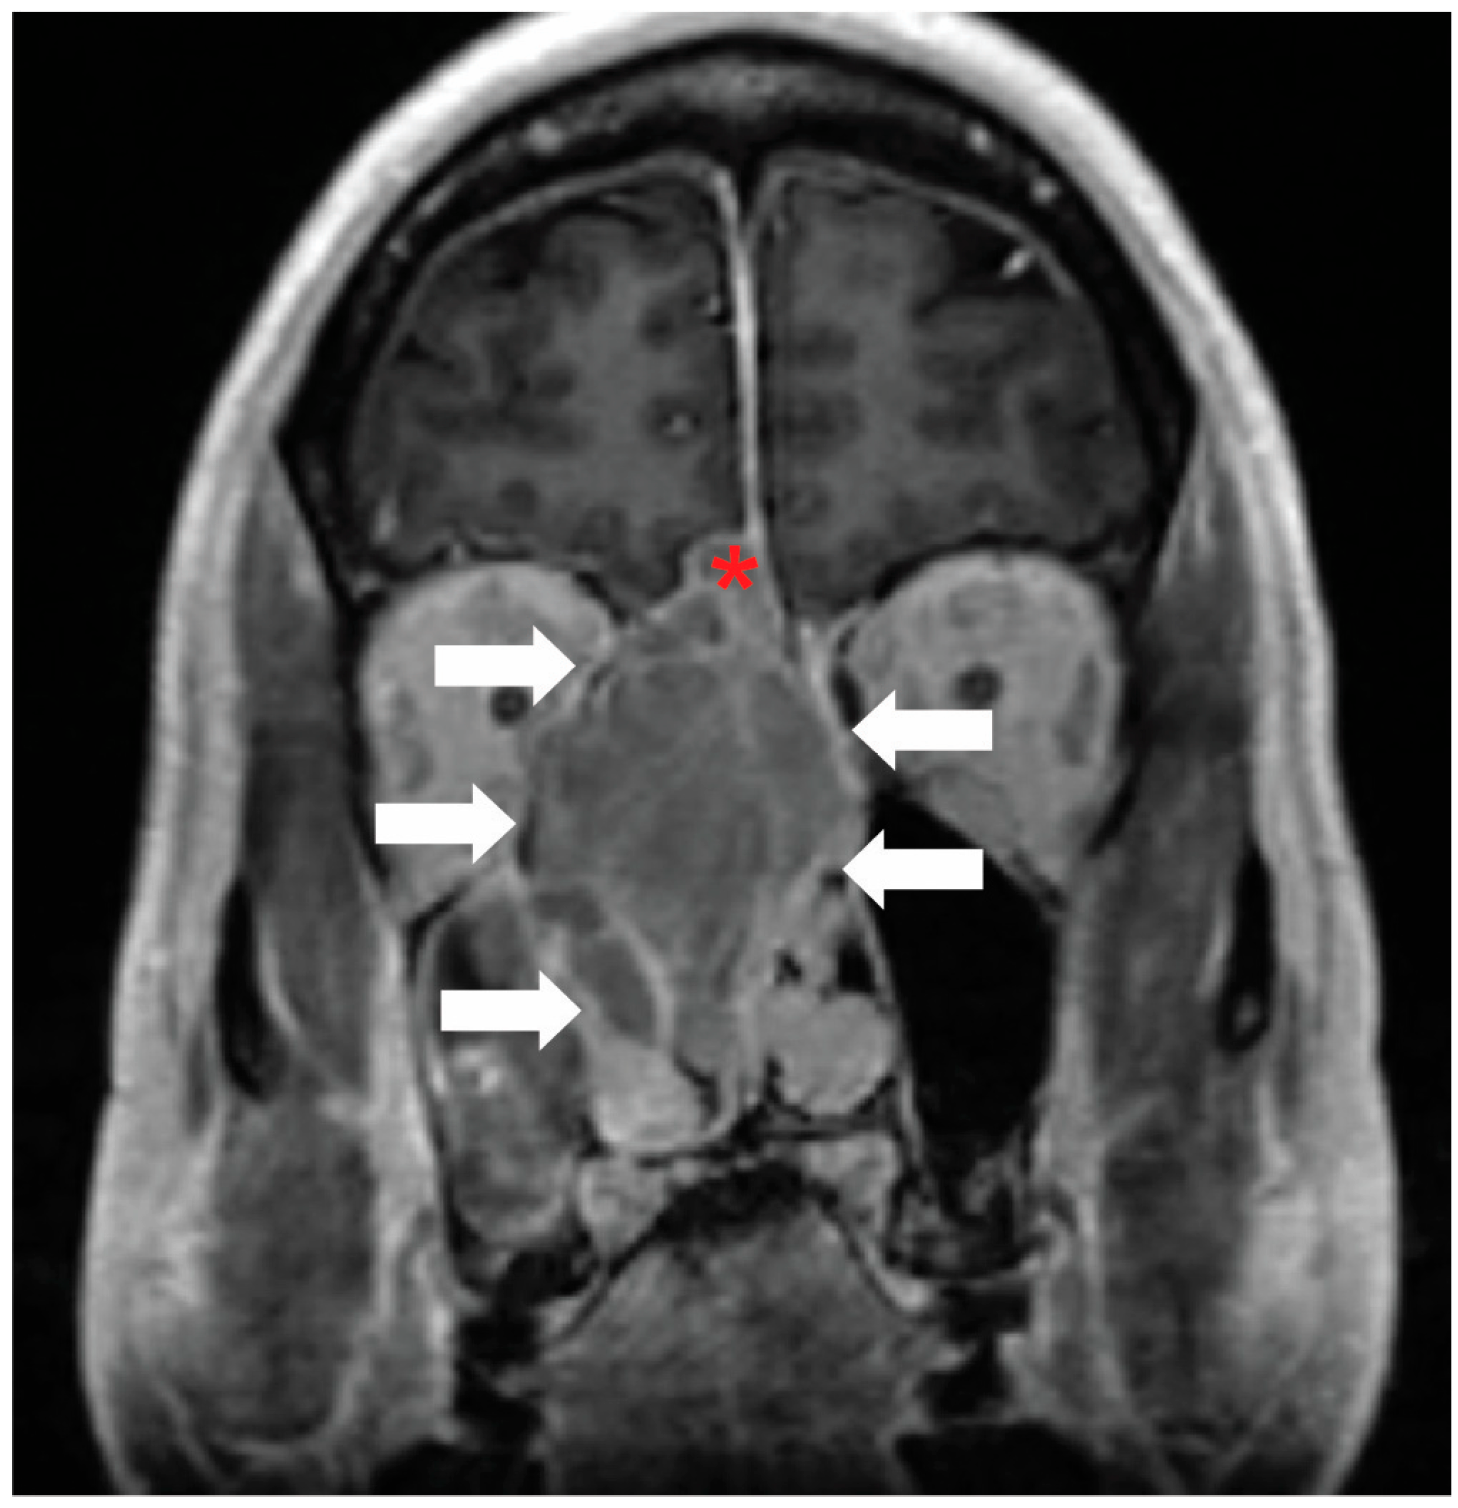

Figure 2. Classical tumor visualization: Contrast-enhanced coronal MRI of the face demonstrates an esthesioneuroblastoma in the right ethmoid air cells (white arrows). There is also intracranial extension (red asterisk). Image and annotations are from the authors.